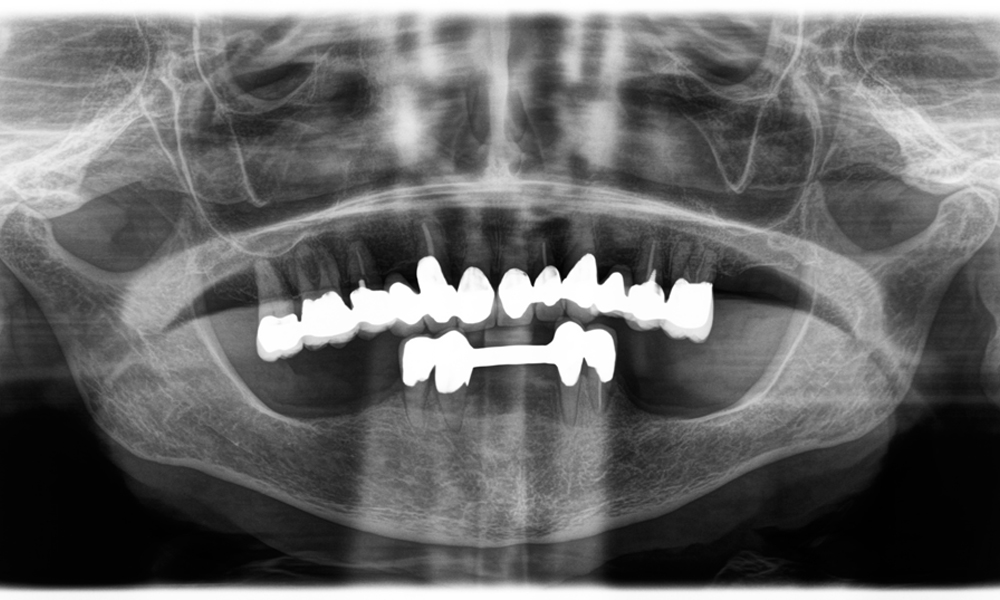

El reto consistía en extraer doce coronas bloqueadas con aleación común sin dañar los raigones subyacentes. Se utilizó el contra-ángulo para realizar incisiones precisas en las capas de cerámica y separar las estructuras metálicas con una fresa de metal duro, con el fin de extraer las coronas con un traumatismo mínimo. En solo 30 minutos se retiraron las coronas antiguas y se pudo preparar el nuevo trabajo, compuesto por zirconio completo en la zona posterior y coronas con recubrimiento en la zona anterior. El resultado fue una reconstrucción completa, satisfactoria tanto desde el punto de vista funcional como estético (véase la fig. 1).